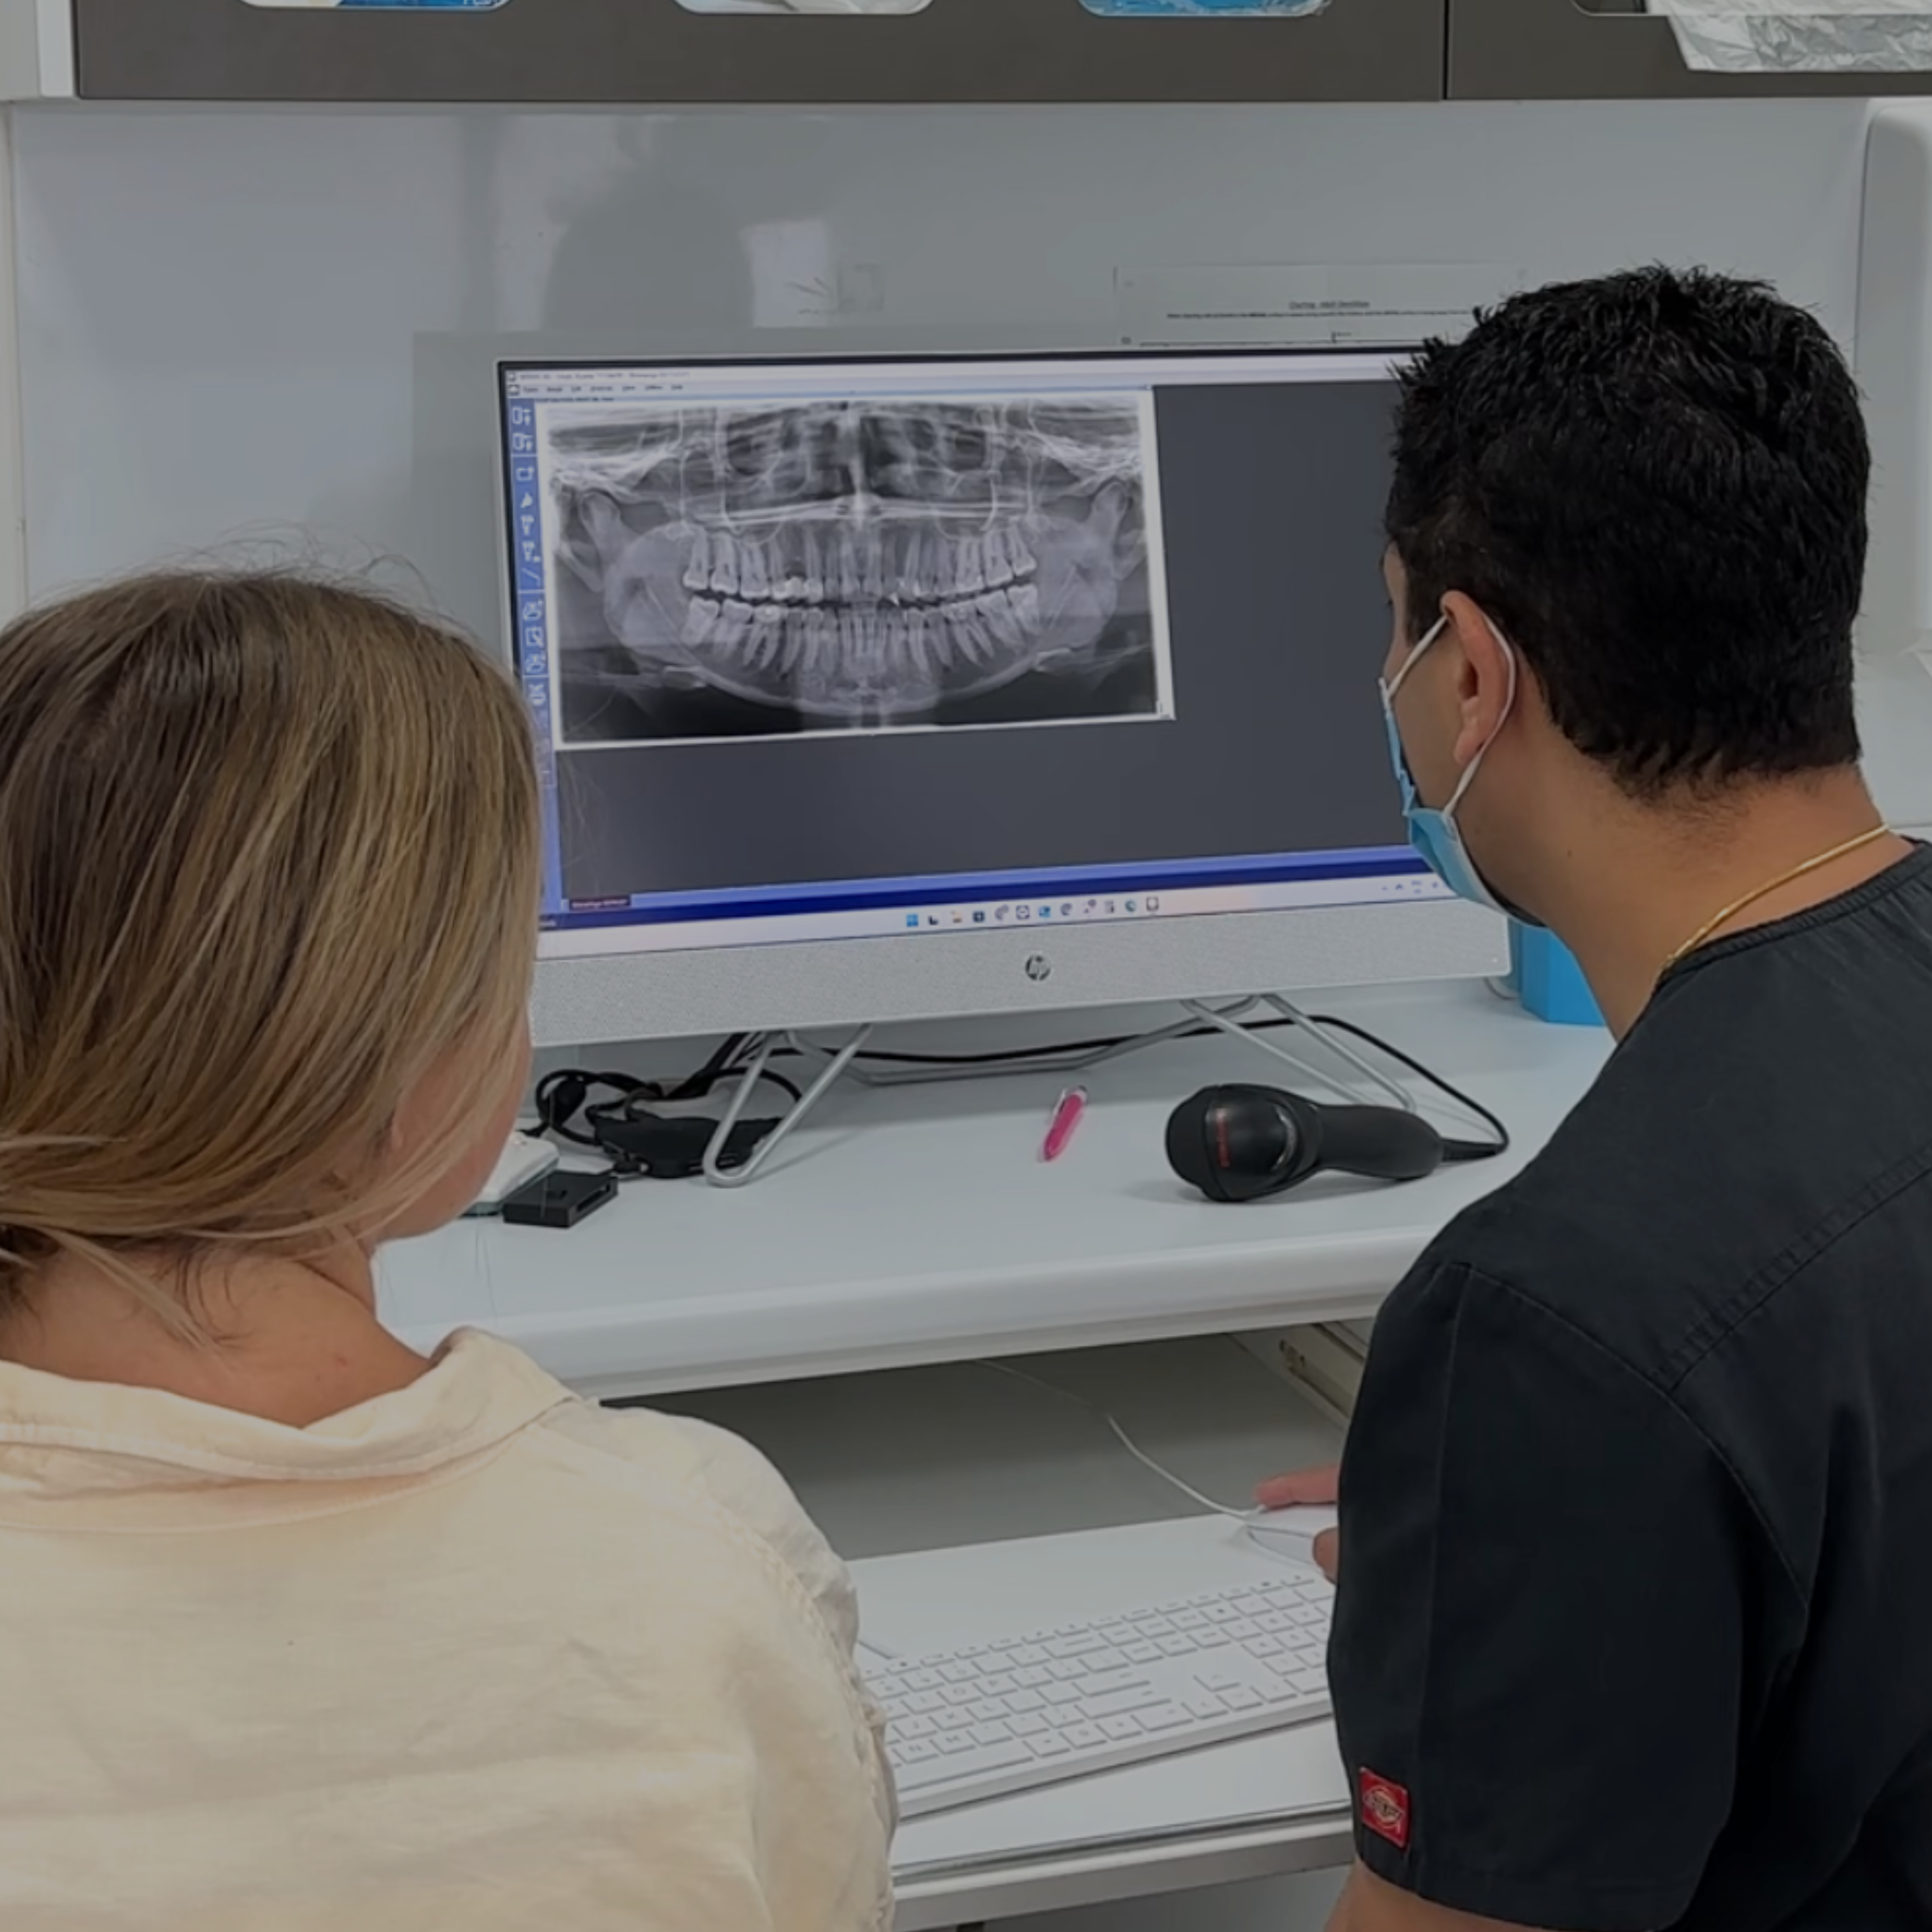

In-Clinic Scan Requirement: To ensure the accuracy and effectiveness of your bonded retainer, a post-treatment digital scan must be taken at an eligible clinic. This is included in the total cost.

Wearing a bonded retainer after treatment is essential for maintaining your newly aligned smile. It helps prevent teeth from shifting back to their original positions (a common issue known as relapse), offering lasting stability—especially for teeth more prone to movement. Bonded retainers are custom-made for a perfect fit, discreetly placed behind the teeth for an invisible finish, and eliminate the need to remember daily wear like removable options. Once your treatment is complete, you’ll visit a clinic for a quick scan to ensure the retainer fits precisely and protects your results for the long term.